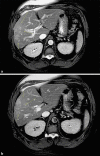

Hepatic inflammatory pseudotumor (IPT) is characterized by a well-circumscribed benign tumor mimicking or often mistaken for a malignant lesion. A 48-year-old male presented to the hospital with complaints of epigastric pain, with initial laboratory findings showing mildly elevated alkaline phosphatase (140 U/L) with normal AST, ALT, bilirubin, and lipase, a CD4 count of 384, and an HIV viral load of > 10 million copies. The total IgG level was elevated to 2,228 mg/dL (normal IgG4 level 114 mg/dL). Contrast-enhanced MRI of the abdomen showed heterogeneous mass-like infiltration in the right lobe of the liver measuring 9.6 cm. The liver mass was biopsied which showed dense collagenous fibrosis with abundant lymphoplasmacytic infiltrates with 18 IgG4-positive plasma cells per high-power field. The patient was not given any treatment for this IPT. For more than 1 year of follow-up triple-phase CT scan of the liver was repeated, which showed no liver mass. As radiological images of hepatic IPTs, including IgG4-related hepatic IPT, mimic liver malignancy, histological analysis of the biopsy remains the cornerstone for the diagnosis. Symptomatic patients with IgG4-related hepatic IPT have shown improvement with corticosteroid use; however, spontaneous resolution has also been reported like in the present case.